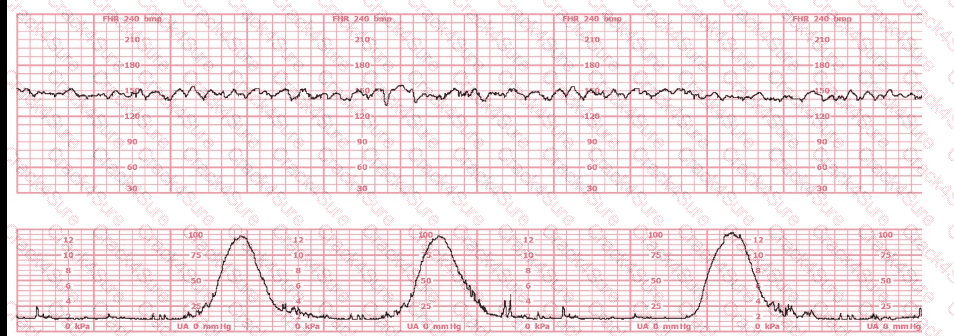

A 30-year-old woman (G2P0) is experiencing preterm labor at 26-weeks gestation. She is receiving magnesium sulfate for neuroprotection. Her external fetal monitoring tracing over the past 30 minutes is shown. The next step would be to: